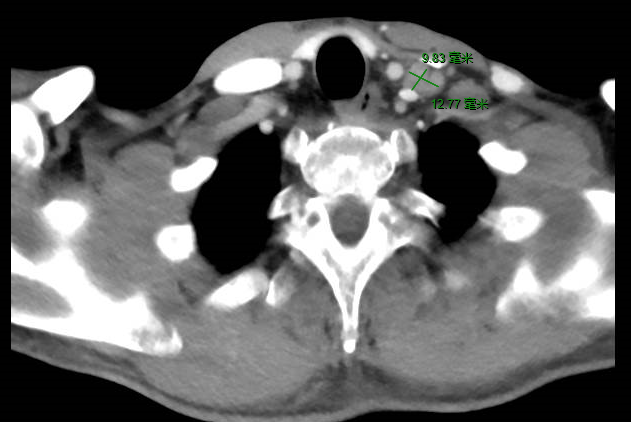

同时发现左颈部和肝脏多发转移灶。

诊断:胃癌术后多发转移(双肺,肝脏,锁骨上淋巴结),Ⅳ期,HER2(+++)。